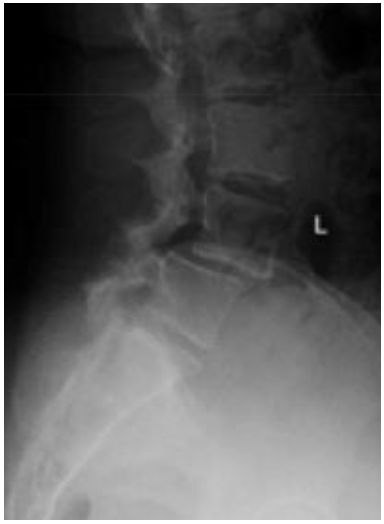

• Quais as principais incidências radiográficas para avaliação da espondilolistese ístimica?

A

• AP + Perfil (em pé)

• Oblíqua (mostra o cachorro de Lachapelle)

• Ap de Fergunson

22

Q

Espondilolisteses

• Na avaliação radiográfica, o que representa o cachorro de Lachapelle na espondilolistese ístimica?

• Visualizado na incidência oblíqua

• Articulação superior → orelha

• Pescoço → pars (fratura = coleira)

• Olho → pedículo

• Focinho → processo transverso

• Processos articulares inferiores → patas

• Corpo → lâmina e processo espinhoso

23

• Na avaliação radiográfica em AP, o que representa o sinal de napoleão invertido?

• Grau 5 de Meyerding → escorregamento completo de L5